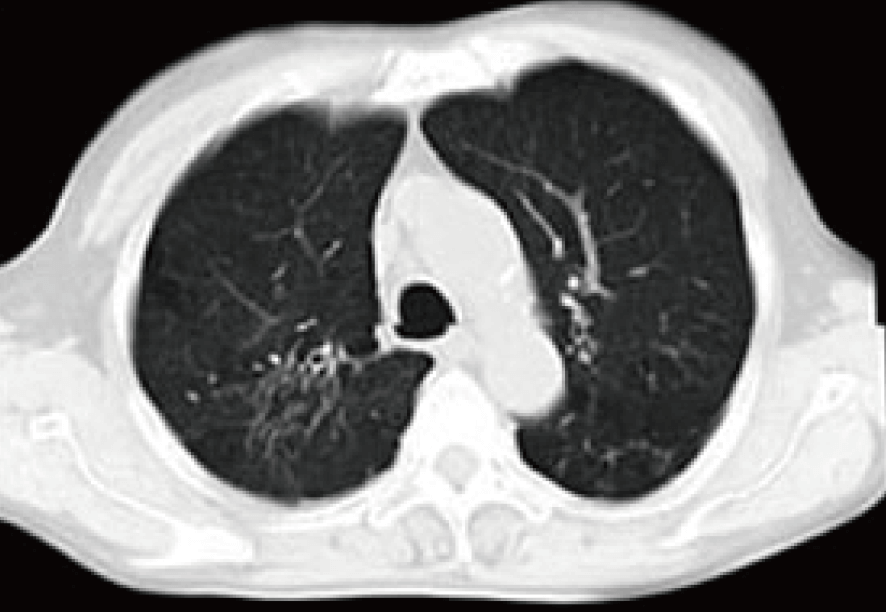

治療前CTでは右肺に大量貯留した胸水が認められる。

提示したCT画像はおよそ6カ月経過後の所見であり、貯留した大量の胸水はほぼ消滅。合わせて腫瘍マーカーもほぼ正常化したため、当外来での内服・点滴治療はいったん終了とした。 引き続き3カ月ごとの画像診断検査、6カ月ごとのリスクチェッカー検査(免疫採血)併用の必要性を指示した。

治療前CTでは右肺の背面に原発性の肺がんと、その周囲のろっ骨浸潤が認められた。

提示した治療後の写真は半年経過時点の胸部CT写真である。